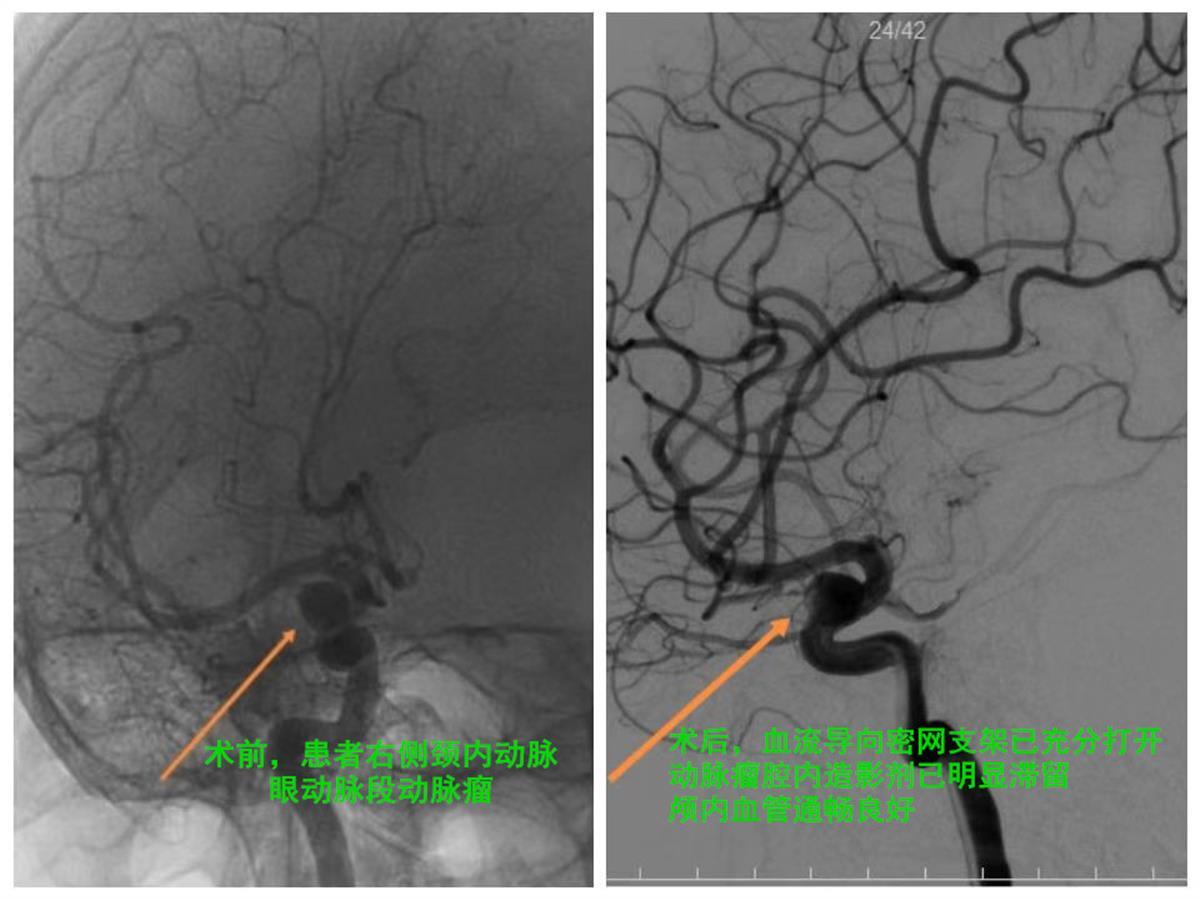

术前术后对比图

经过周密的术前准备,肖国民带领神经介入团队在不到一小时的精心操作下,便顺利完成了手术。术后即刻复查造影显示血流导向密网支架已充分打开,各段均贴壁良好,动脉瘤腔内造影剂已明显滞留,颅内血管通畅良好。次日徐女士即可下床活动,头痛明显缓解,超前解决了颅内隐忧。